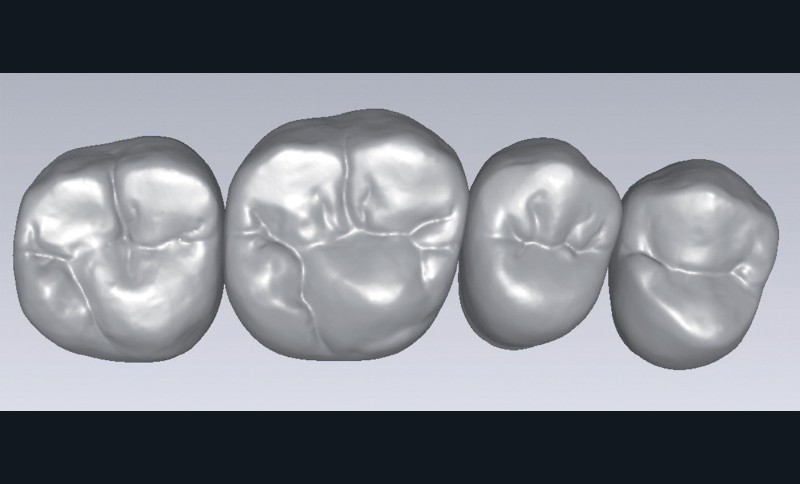

que = prothèse complète. Cette idée préconçue n’est plus vraie. De nos jours, la prothèse gériatrique se décline sur tous les types de prothèses amovibles, y compris les appareils complets implanto-retenus. Ceci signifie que les prothésistes dentaires, mais aussi les fabricants de dents prothétiques, sont confrontés à de nouveaux défis (fig. 1 à 4).